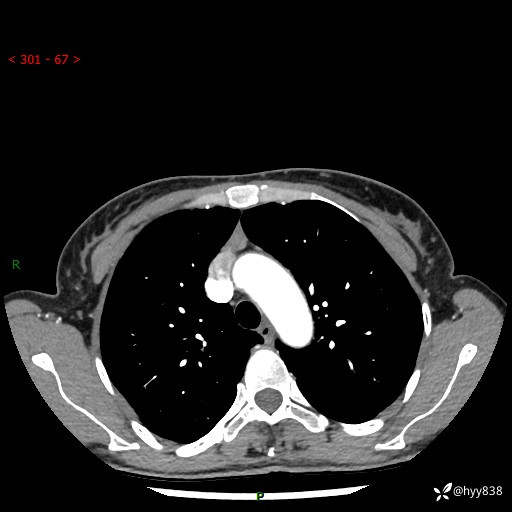

增强动脉期+静脉期